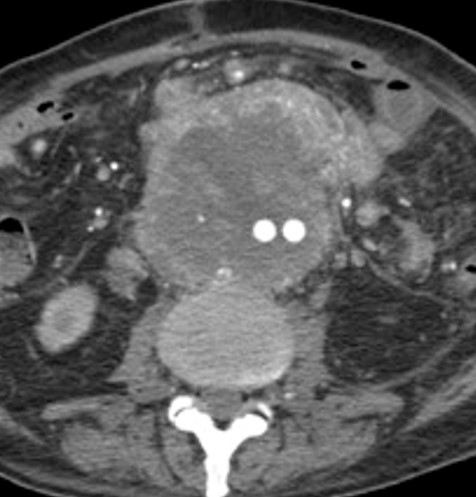

• 大動脈の右側、内膜石灰化よりも外側に、造影効果を有する占拠性病変を認める

• Mural type:血管の外側に存在する結節状・三日月状の腫瘤

• 血管新生による造影効果

• 初回CT

• 22日後のCT